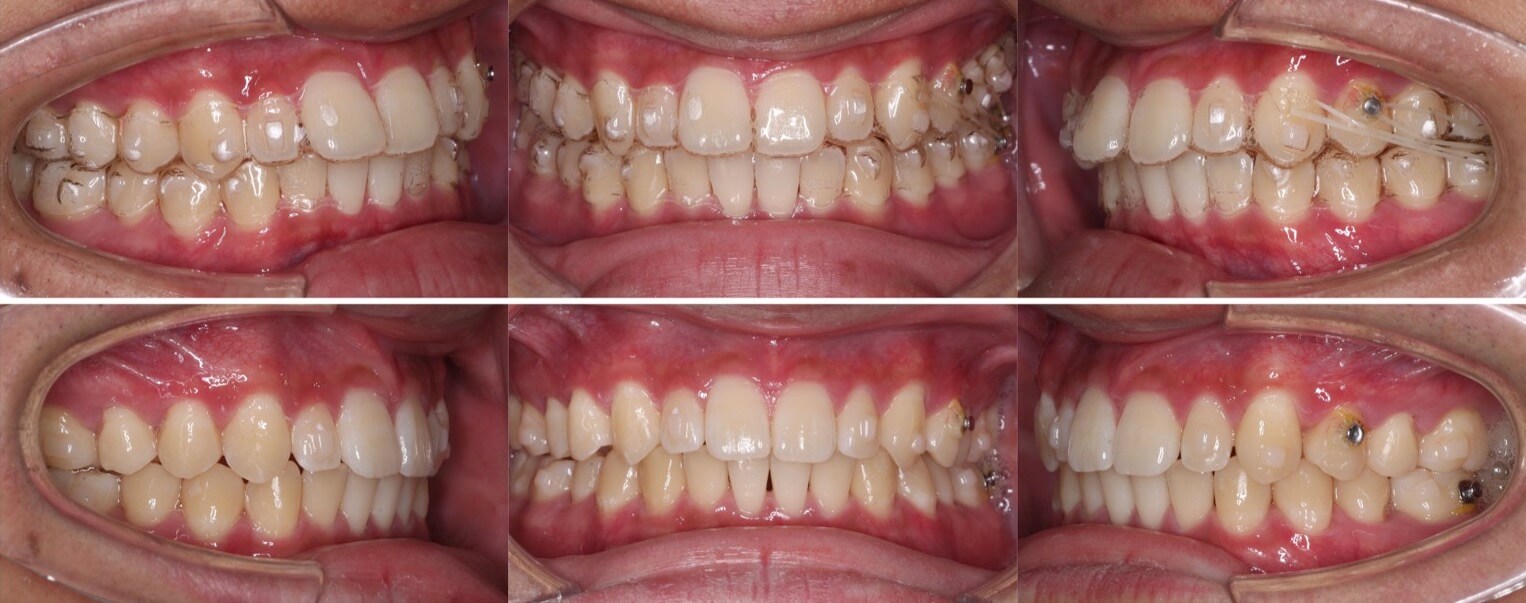

隙間が上下奥歯まであり難しいケースになります。このような出っ歯傾向がある空隙歯列は、マウスピース型矯正装置の適応症です。また、10代男子であればあご骨格の成長量が残っており利用して前歯の前突の改善もできます。過蓋咬合も治り、スマイルの印象も変わりました。

症状:正中離開・過蓋咬合

治療方針:空隙閉鎖+下顎歯列前方移動

治療装置:マウスピース型矯正装置(アライナー装置)

固定装置:II級顎間ゴム

治療期間:1年7か月

アライナー枚数:58+26ステージ (7日交換)